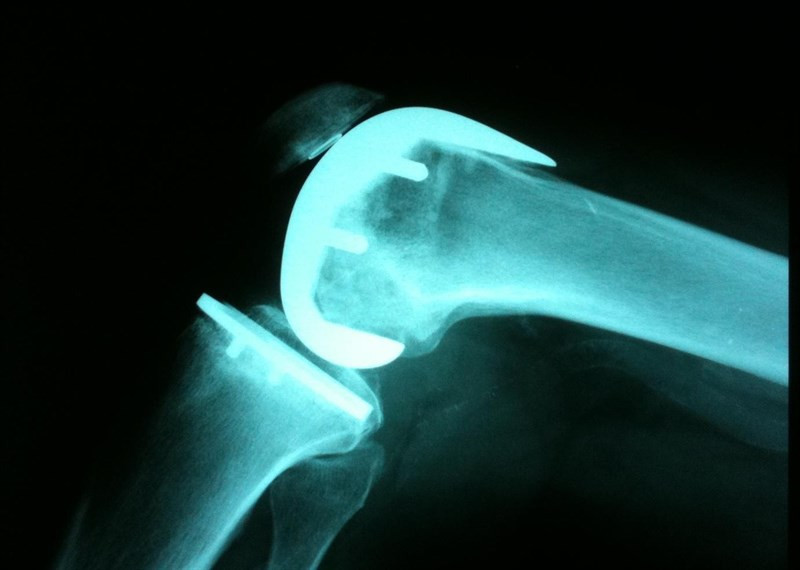

Rodillaradiografiarayos

Imagen de archivo de una radiografía